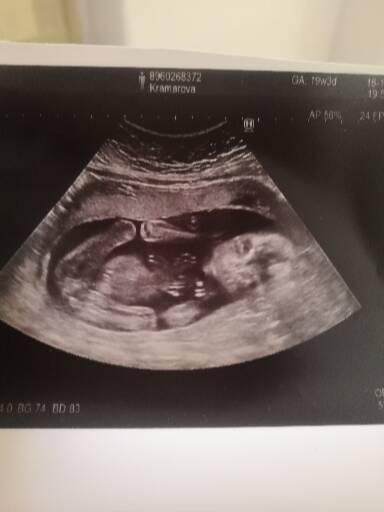

Ja som si robila na deviaty deň a už bola slabšia druha čiarka. Zatiaľ som 5tt a netrpezlivo čakám ešte dva týždne na sono či je všetko ok

Ahojte baby. Ja som mala ivf tento rok, prvý pokus nevyšiel to bolo v máji. Najprv som mala od 5 dňa slabú druhú čiarku,ktorá začala slabnut a aj krv bola potom negatívna. Druhý pokus bol vklad dvoch embryjok v auguste. Ten vyšiel, ale zaujímavé bolo že som si urobila test na 7 deň a nebolo tam nič. Už som sa zmierovala s tým,že opäť sa nepodarilo. Potom na 9 deň som už len tak ani neviem prečo urobila znova test a už bola jasná druhá čiarka. Aj krv bola pozitívna mala som hcg vyše 800. Uchytilo sa ale len 1 embryo z dvomi vložených. Momentálne som 20 týždeň tehotenstva a zatiaľ vyzerá byt všetko v poriadku, a vyzerá to tak že čakáme dievčatko 😊 Takže nezúfajte,viem aké to je a každej držím palce strašne ❤️